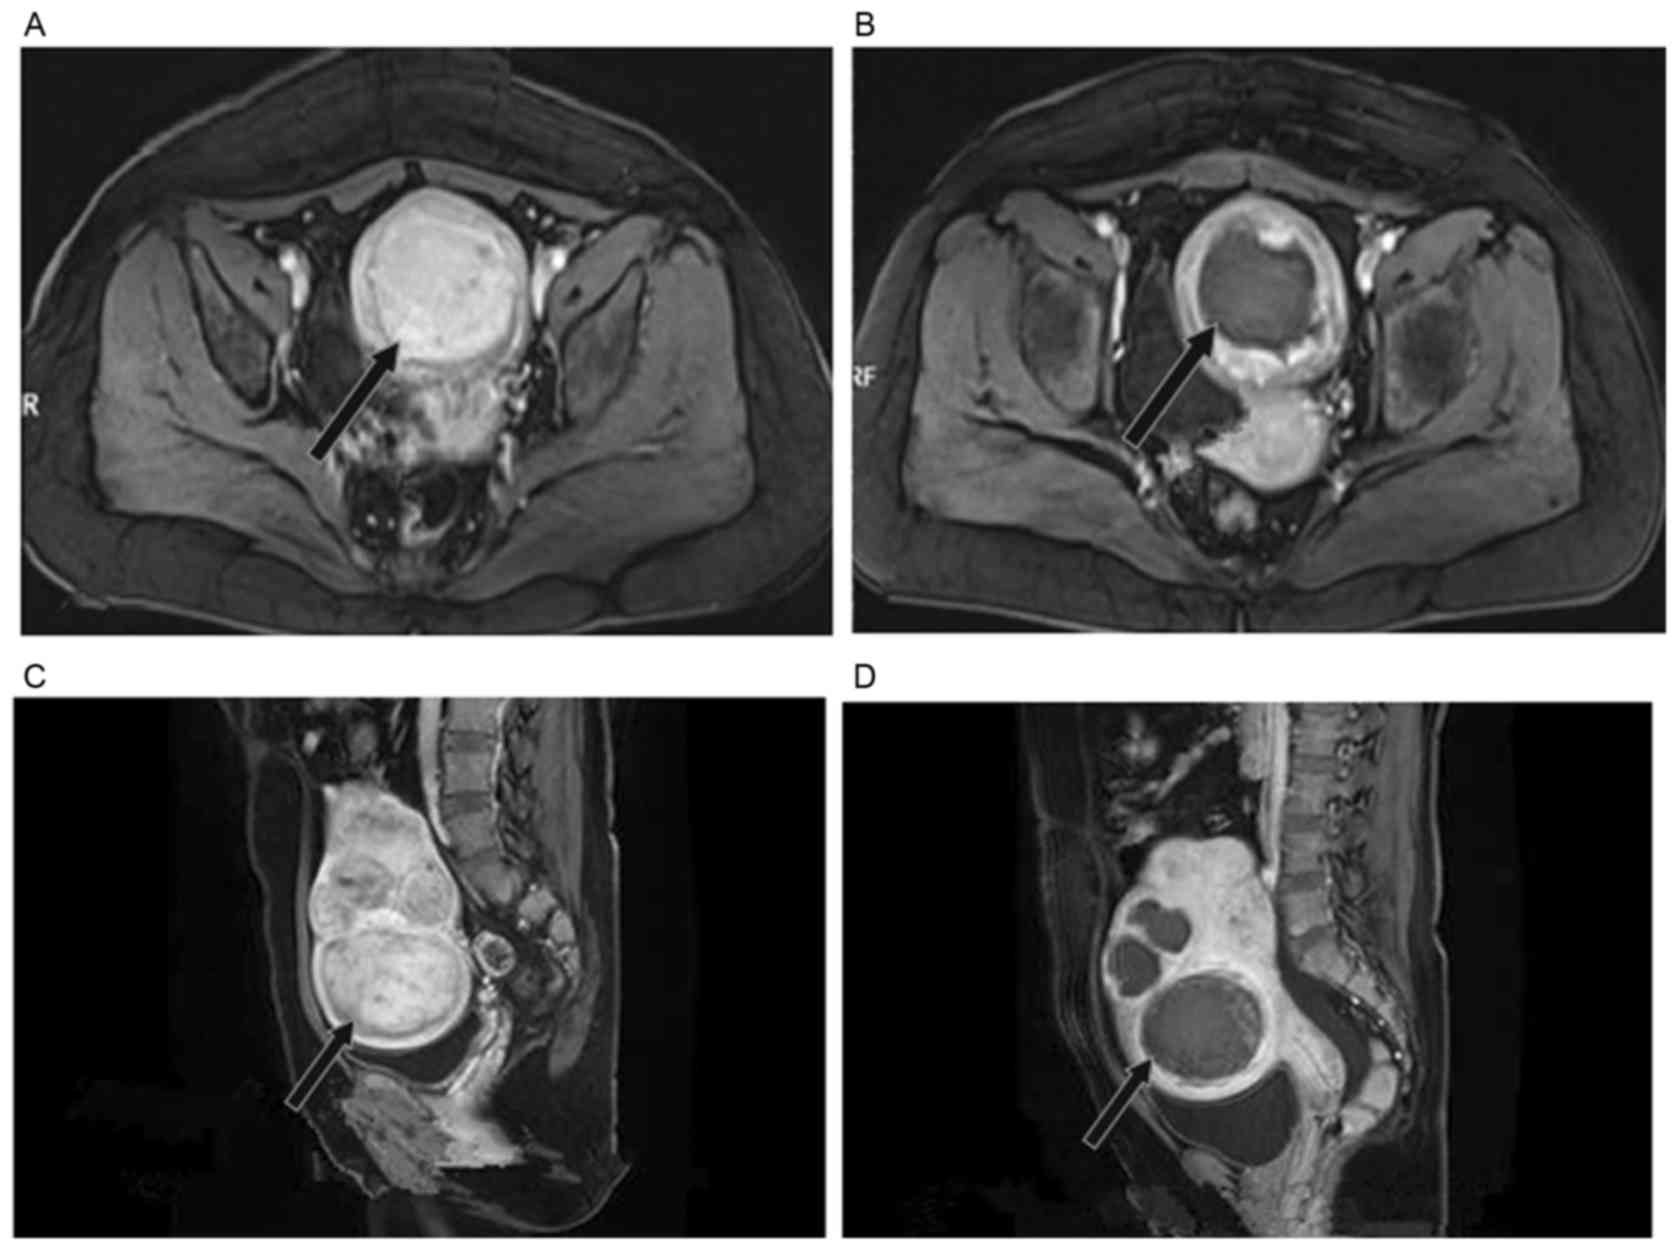

Sagittal T2 Weighted Images Of A Patient With A Very Large Fibroid That Download Scientific Diagram

www.researchgate.net